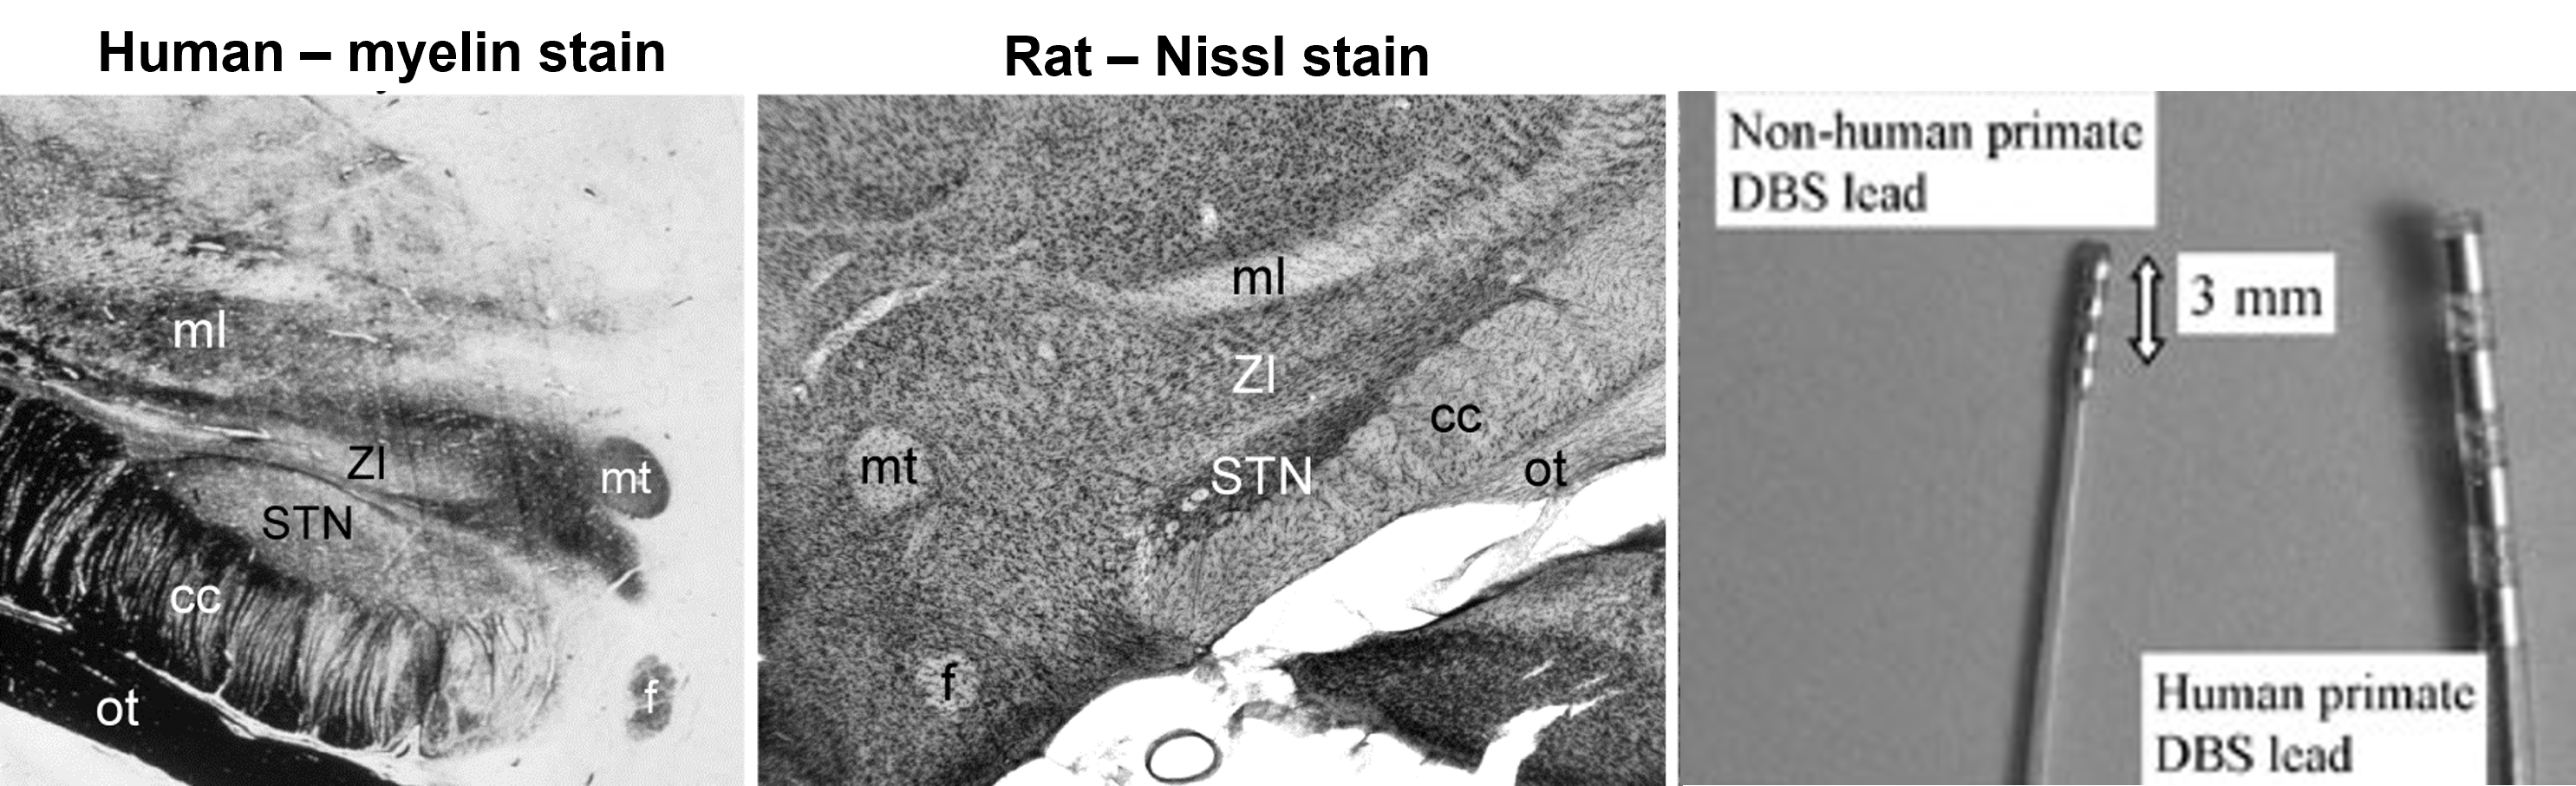

the anatomy of the basal ganglia has prompted several strategies for treating parkinson’s disease

Microelectrode Stimulation

subthalamic stimulation

A potential problem with a ventral pallidotomy is that the optimal site for the lesion is located close to the optic tract and it may produce homonymous hemianopsia.

chronically implanted electrodes targeting the STN to treat Parkinson’s disease will also stimulate the zona incerta